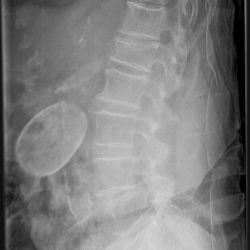

Porzellangallenblase